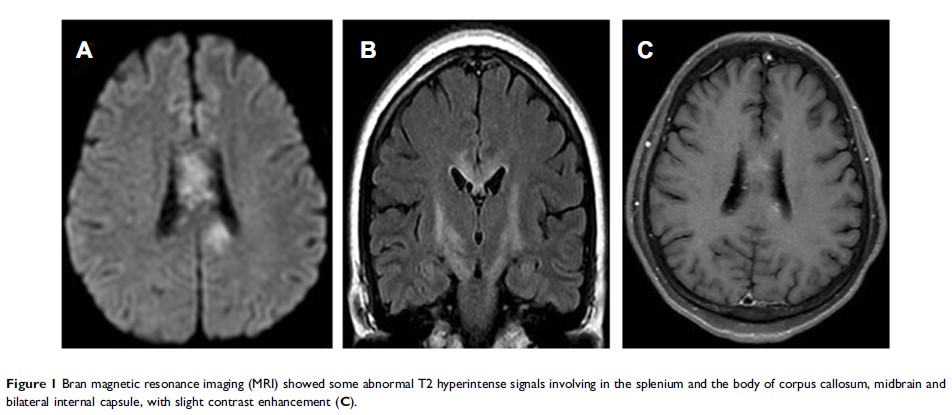

乳腺癌伴视神经脊髓炎谱系疾病副肿瘤性神经综合征